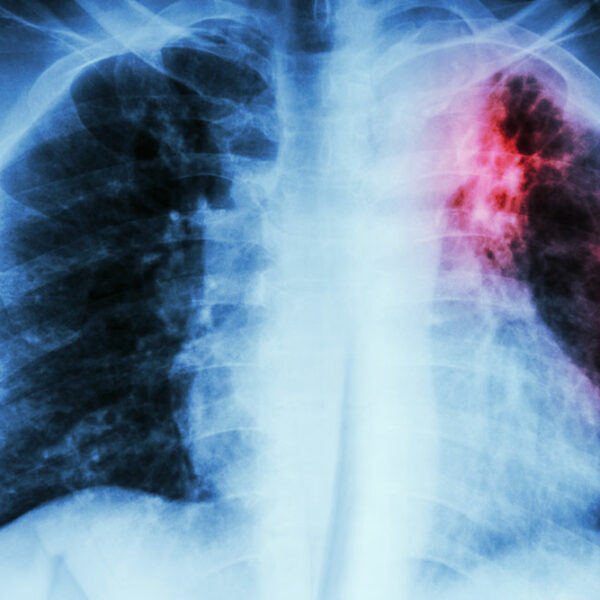

It is an ultrasound test for the heart. - Chest X-ray

This non-invasive technique provides a clear and detailed picture of your heart and lungs which the doctor can examine to detect any problem. - Computerized Tomographic Angiography